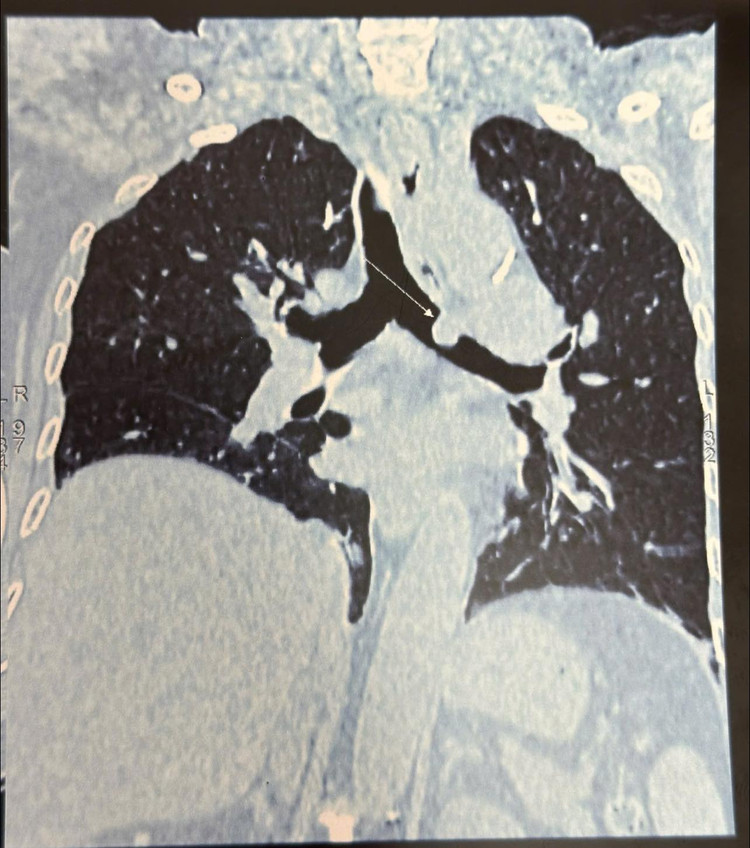

Nhận định về trường hợp này, TS.BS Nguyễn Khắc Kiểm, Trưởng khoa Ngoại lồng ngực cho biết “Khối u nằm ở vị trí phế quản gốc trái cách Carina 1cm lồi vào lòng phế quản do đó chúng tôi đã hội chẩn, nhận định phương án phẫu thuật cho người bệnh để đảm bảo hiệu quả nhất.

Xác định đây là một ca ung thư phổi giai đoạn sớm, vị trí như vậy không thể phẫu thuật cắt u theo phương pháp thông thường, đòi hỏi phải cắt, nối và tạo hình phế quản bảo tồn thùy phổi.”

| Tốn thương ung thư phổi trên phim chụp - Ảnh BVCC |

Đánh giá tổn thương trong mổ: u tại vị trí phế quản gốc trái kích thước 1cm cách Carina 1,5cm u lồi vào lòng phế quản, kíp mổ quyết định cắt đoạn phế quản gốc dài 1,5cm và nối hai đầu phế quản được cắt rời, ca mổ được thực hiện trong 3h với sự tập trung và quyết tâm cao nhất của cả ekip.